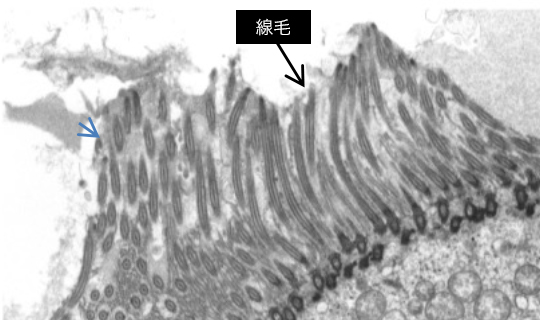

透過型電子顕微鏡(TEM)および走査型電子顕微鏡(SEM)を用いた電子顕微鏡解析を行います。標本作製から写真撮影・観察・評価まで対応します。

また、pre-embedding法およびpost-embedding法による免疫電子顕微鏡検査も可能です。2重染色法にも対応可能です。

TEM写真例

モルモット鼻腔(

fig.1

)(

fig.2

)

fig.1 呼吸粘膜細胞

fig.2 繊毛